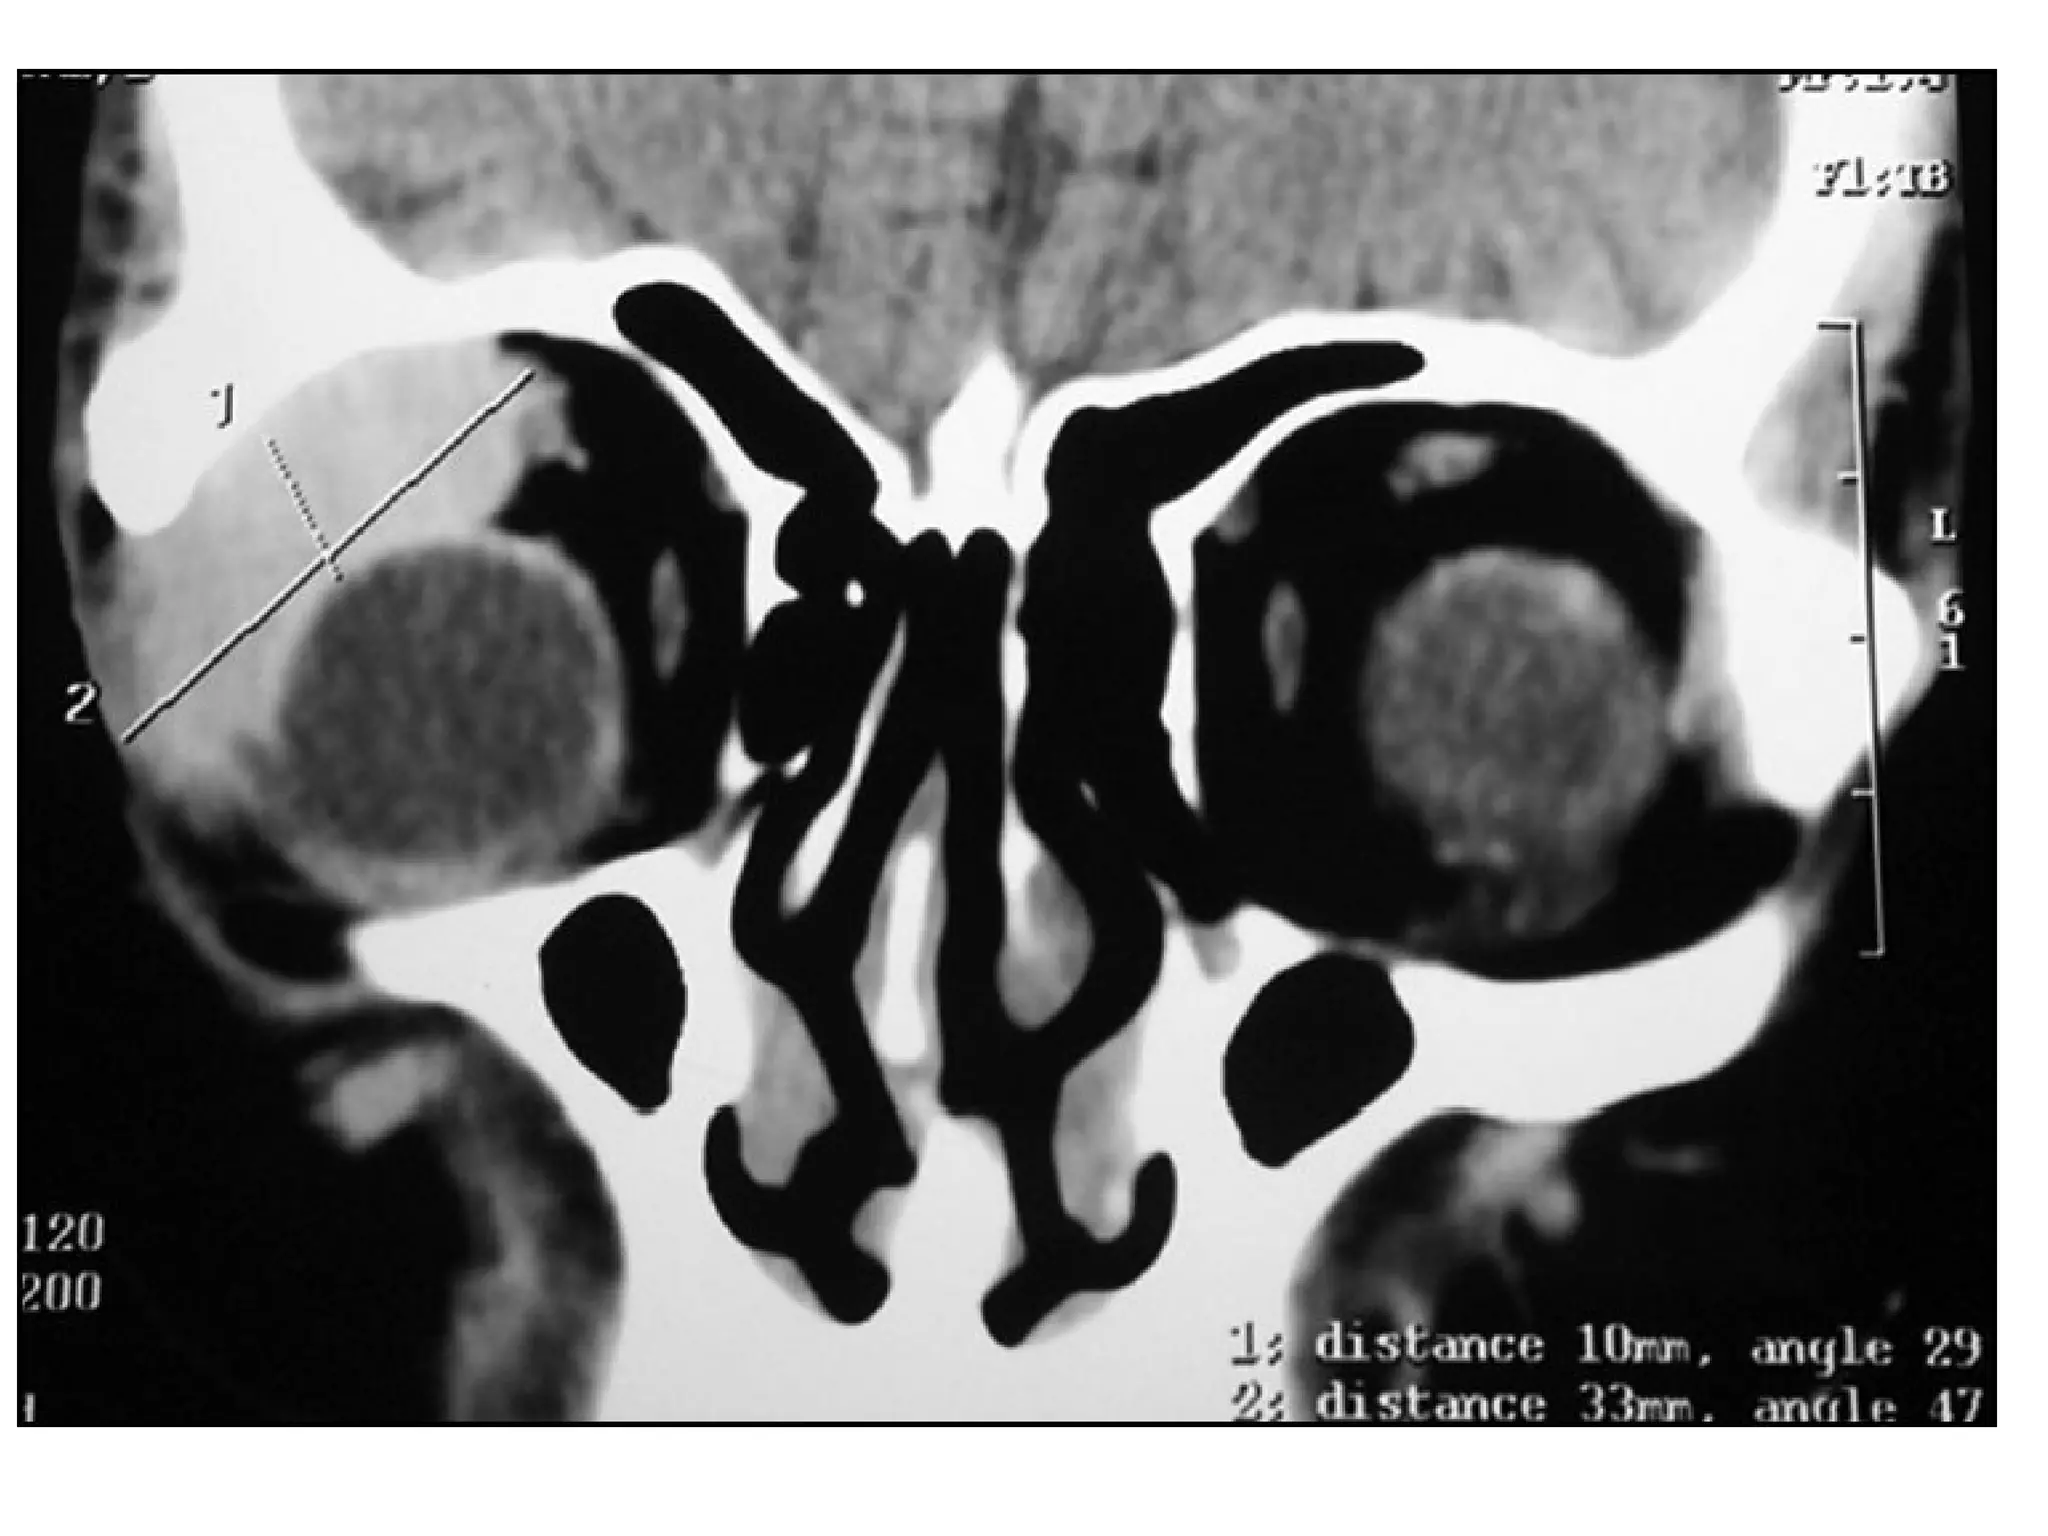

1-CT :

-Intraocular high density (calcification , hemorrhage)

mass

-Over 90% of tumors show calcification on CT which may

be small , large , single or multiple

-Diffuse infiltrating tumors are less likely to show

calcification

-Intraocular calcification in children under 3 years of age

is highly suggestive of retinoblastoma